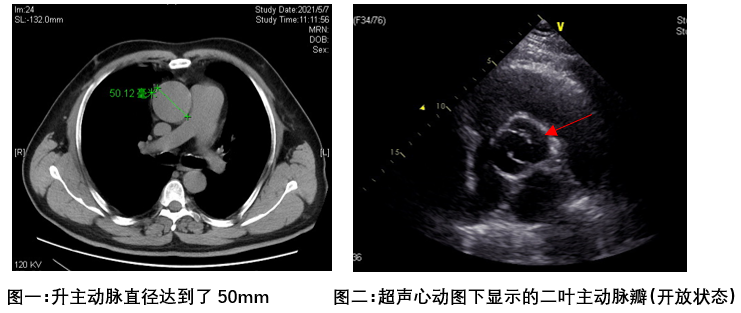

北京清华长庚医院6月9日电(通讯员 杨栩鹏)家住青海的吴先生,最近频繁出现活动后的胸闷和气短。起初他以为是冠心病,并没有引起重视,但随着症状逐渐加重,便到了当地医院就诊。冠心病相关的检查并没有明显异常,但是在做心脏超声时,发现了更严重的问题:主动脉瓣二叶瓣化畸形和升主动脉瘤。

显然吴先生恰恰就是这1/200概率中的一员。就目前的指南及专家共识来说,主动脉瓣二叶瓣化畸形 主动脉瓣返流,合并升主动脉50mm,已经达到了手术治疗的指征,如果不及时治疗,升主动脉继续瘤样扩张,可能会有主动脉夹层甚至破裂的风险。而治疗此疾病最好的手段,便是更换损坏的主动脉瓣膜,同时替换扩张的升主动脉。手术难度系数高,风险较大,当地医院无法进行,所以吴先生慕名来到了北京清华长庚医院。

清华长庚医院心脏外科大血管组负责人崔晓征医师主导评估了他的病情。针对此类疾病,临床上有多种手术方式,评估何种方式最佳需根据每个患者的具体病情敲定。根据CT下升主动脉测量数据达到了50mm,主动脉瓣超声下确实是二叶瓣化畸形,冠脉造影评估回报吴先生并未合并冠状动脉狭窄,崔晓征医师为吴先生选择了主动脉瓣机械瓣置换+升主动脉人工血管置换术(又称为“Wheat’s手术”),最大限度地保证了吴先生冠状动脉血供不受影响,同时缩短了手术时间,提高了手术安全性。目前吴先生术后恢复良好,已顺利出院。